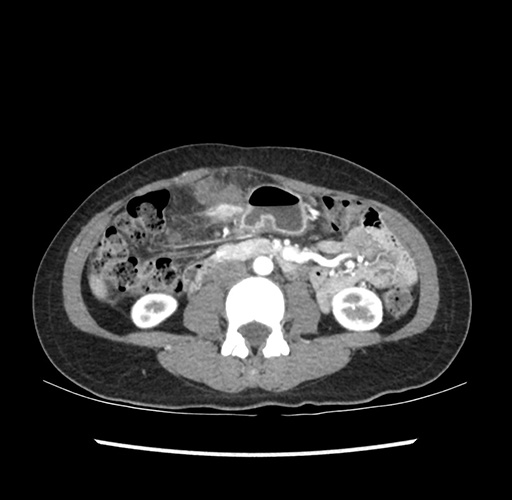

Imaging Analysis

Look through the patient's CT scan to identify any areas of concern for the necessary procedure.

Based on your CT findings, which issue(s) would give reason for "planned slowing down moment(s)" in this case?

Considering a standard left lateral sectionectomy procedure, what step(s) of the operation would you do differently in this case ?